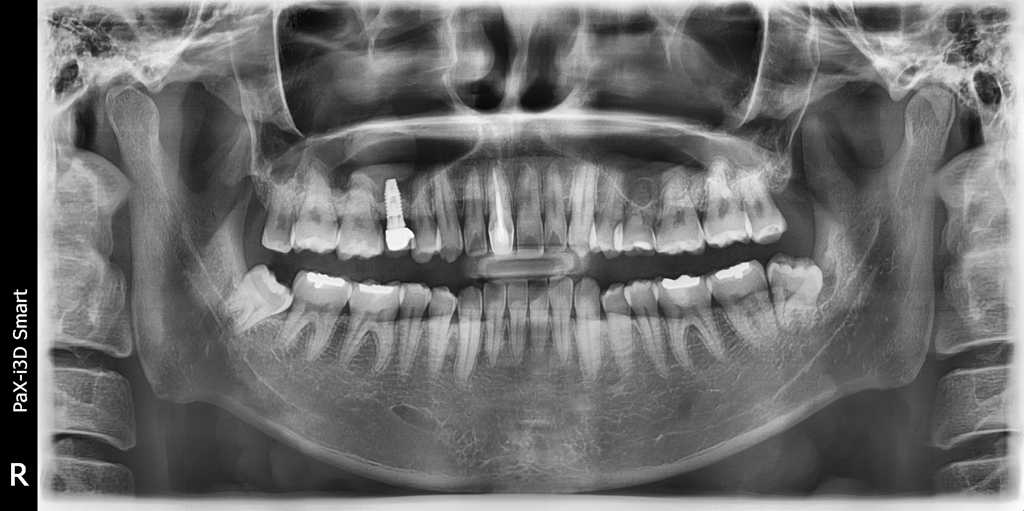

유치로 인해 임플란트 한 후 10여년이 지났는데요

파노라마 x-ray 사진상

임플란트를 중앙 윗니 기준4번째 어금니에 했는데요

유난히 3번째 치아 부위의 잇몸만 유난히 튀어나와있는데요

이유가 몰까요?

임플란트랑 연관이 있을까요?

임플란트 떄문에 그럴가능성은 없을것같습니다. 원래 그랫을수도 잇고 수술하면서 잇몸이 과증식되서 그럴수도 잇습니다 .

세 번째 치아는 송곳니입니다 송곳니는 뿌리가 깊고 앞쪽으로 위치해 있기 때문에 송곳니가 있는 부위에 잇몸은 다른 곳보다 앞으로 나와 있는 경우가 있습니다.

크게 문제가 되진 않지만 걱정이 된다면 치과에서 자세한 검사를 받아 보는 것이 좋습니다.